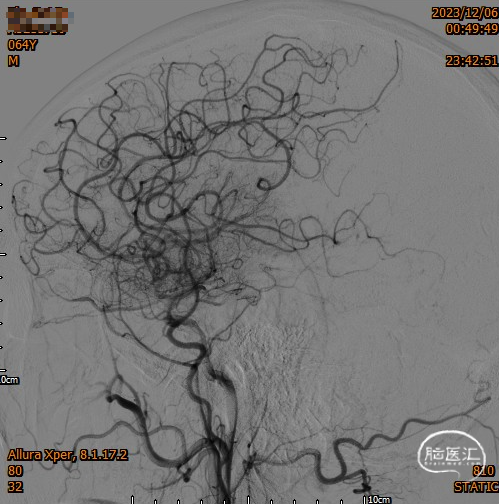

造影,颈内动脉未见血栓,颅内动脉较前未见明显减少,无明显血栓逃逸。

复查造影支架成形良好,颅内较前无明显改变,未发现血管减少影像,供血较前明显改善。